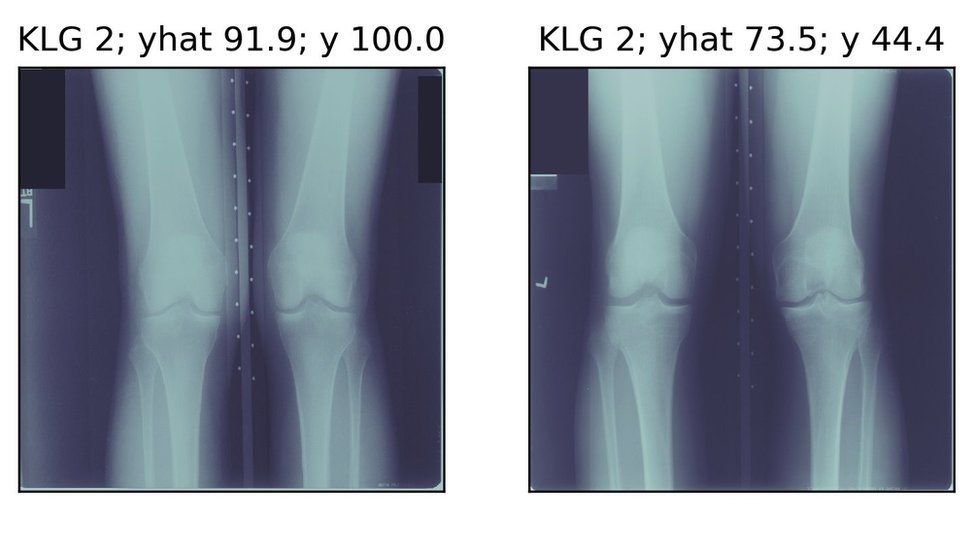

연구진은 AI 기술을 사용해 무릎 골관절염 환자들을 대상으로 이들이 겪는 통증의 정도를 예측하기 위해 무릎 엑스레이 사진을 분석했다. 환자 4,172명으로부터 3만6,369개에 달하는 엑스레이 이미지를 수집해 활용했다. 그 결과 컴퓨터 분석을 통해 방사선 전문의가 간과하고 놓친 부분을 잡아낼 수 있었다는 게 연구진의 설명이다.

그런데 AI 알고리즘으로 분석한 결과, 통증 정도가 비슷해 보였던 환자들이 실제로 보이는 것과는 다를 수 있다는 사실이 드러났다. 다시 말해 기존의 방사선 평가 시스템을 사용하는 의사들은 진단하지 못하고 간과할 수 있는 병의 다른 특징들까지 AI 알고리즘이 고려할 수 있다는 것이다.

흑인 환자 집단의 경우 환자 본인도 심각한 통증을 호소하고 AI 알고리즘도 높은 통증 점수를 매겼음에도 불구하고 기존 방사선 평가 시스템에서는 낮은 통증 점수를 받는 사례가 많았다. 이는 통상적인 기존 진단 방식이 흑인 환자에게 적합하지 않고 불리하게 작용할 수도 있다는 점을 시사한다.